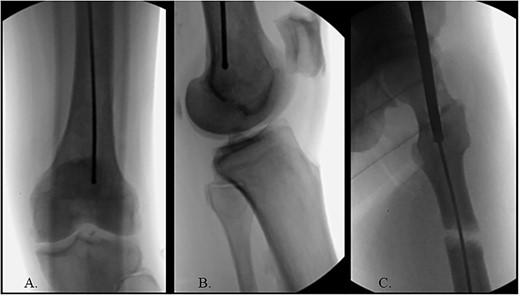

The patient was positioned supine on a fracture table. A guide wire was inserted through a 4-cm surgical incision proximal to the greater trochanter (GT) and was passed through a cannulated awl in a position slightly medial to the tip of the GT on the AP and center on the lateral (Fig. 2B). A (15-mm) entry reamer widened the opening (Fig. 2C). A rigid cannulated reduction rod and forceful malleting allowed the ball-tipped guidewire to cross the close reduced fracture, but too lateral and posterior distally (Fig. 3A and B). The cannulated flexible reamers encountered impassible blastic lesions within the proximal femur (Figs 3C and 5B).

(A) Cannulated awl positioned medial to tip of GT on the AP XR; (B) cannulated awl positioned center of GT on the lateral XR; (C) entry reamer over guide pin on the AP XR.